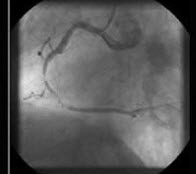

下面一组图像应考虑为( )

A:正常的肺动脉瓣

B:正常的二尖瓣

C:正常的三尖瓣

D:正常的主动脉瓣

E:可见两个瓣膜